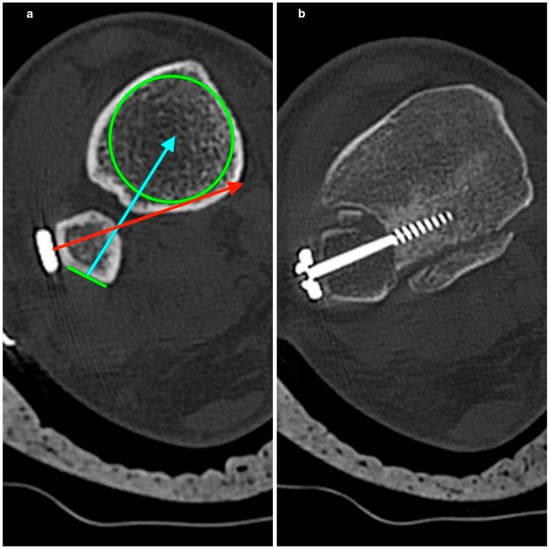

3.2. CT Evaluation